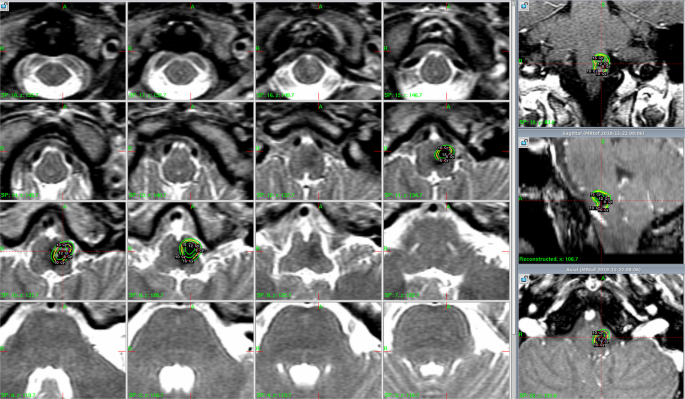

A total of 52 symptomatic hemorrhages occurred in 43 patients during this period (0.16 symptomatic hemorrhages/patient). Among these, 15 symptomatic hemorrhages occurred within 2 years after GKS, whereas 37 symptomatic hemorrhages occurred >2 years after GKS. The annual incidence of symptomatic hemorrhage during the first 2 years after GKS was 3.22% (15 hemorrhages/465.40 patient-years). The annual incidence of symptomatic hemorrhage after the initial 2-year follow-up was 3.16% (37 hemorrhages/1169.68 patient-years). Figure 1 illustrates the changes in annual incidence of hemorrhage before and after GKS. Figure 2 illustrates a case of a patient with brainstem CCM who presented with symptomatic hemorrhage treated with GKS.

A 27-year-old female presented with a sudden onset of left limb weakness and numbness, gait disturbance, diplopia, and facial numbness for one week. A CCM with associated hemorrhage that measured 3.5 mL in volume was found in the medulla. T2-weighted imaging on MRI demonstrated a hemosiderin ring around the CCM. The CCM was treated using GKS with a margin dose of 10 Gy at a 55% isodose level. The CCM was controlled for up to 63 months.

Radiosurgery was performed using the Leksell Gamma Unit Model C (Elekta Instrument, Inc). The median lesion volume was 3.1 ml (0.03–28.9 ml). Figure 2 presents a typical dose plan for a representative case. The prescription dose was set at an isodose level of 50–90%, and the median margin dose was 11.9 Gy (range 8.5–18 Gy). A higher margin dose (>12 Gy) was avoided due to the benign nature of the lesions and used only in the early part of this study. A higher margin dose (>12 Gy) was avoided due to the benign nature of the lesions and used only in the early part of this stud To achieve a highly conformal dose distribution, multiple small shots were used to maximize the mean dose and minimize the radiation volume outside the target. No identifiable portion of the facial nerve received more than 13 Gy and the trigeminal nerve received no more than 15 Gy. The margin dose administered to tumors that bulged into tissue of the brainstem was reduced to 11 Gy. y. To achieve a highly conformal dose distribution, multiple small shots were used to maximize the mean dose and minimize the radiation volume outside the target. No identifiable portion of the facial nerve received more than 13 Gy and the trigeminal nerve received no more than 15 Gy. The margin dose administered to tumors that bulged into tissue of the brainstem was reduced to 11 Gy.